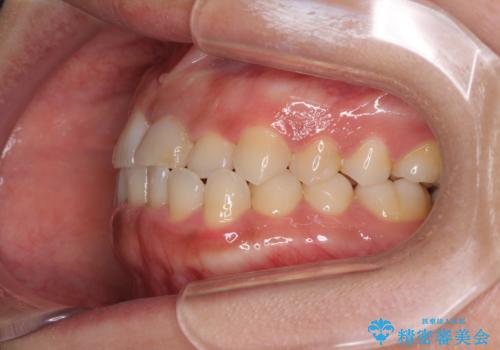

前歯の反対咬合 非抜歯のワイヤー矯正

- 前歯のでこぼこを気にして来院された患者様です。

1年半はかかると思っていた治療期間ですが、反対咬合となっている前歯が思いの外早く動き、僅か9ヶ月で終了させることができました。

前歯を気にせず笑えるようになり、患者様には大変満足していただきました。